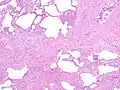

The histologic hallmarks of UIP, as seen in lung tissue under a microscope by a pathologist, are interstitial fibrosis in a "patchwork pattern", honeycomb change and fibroblast foci (see images below).[6][7]

Appearance of usual interstitial pneumonia (UIP) in a surgical lung biopsy at low magnification. The tissue is stained with hematoxylin (purple dye) and eosin (pink dye) to make it visible. The pink areas in this picture represent lung fibrosis (collagen stains pink). Note the "patchwork" (quilt-like) pattern of the fibrosis. -

Appearance of honeycomb change in a surgical lung biopsy at low magnification. The dilated spaces seen here are filled with mucin. Hematoxylin-eosin stain, low magnification. -

A fibroblast focus in a surgical lung biopsy of UIP. Hematoxylin-eosin stain, high magnification. The white space to the left is an airspace. The pale area to the right is a fibroblast focus. It is an area of active fibroblast proliferation within the interstitium of the lung.